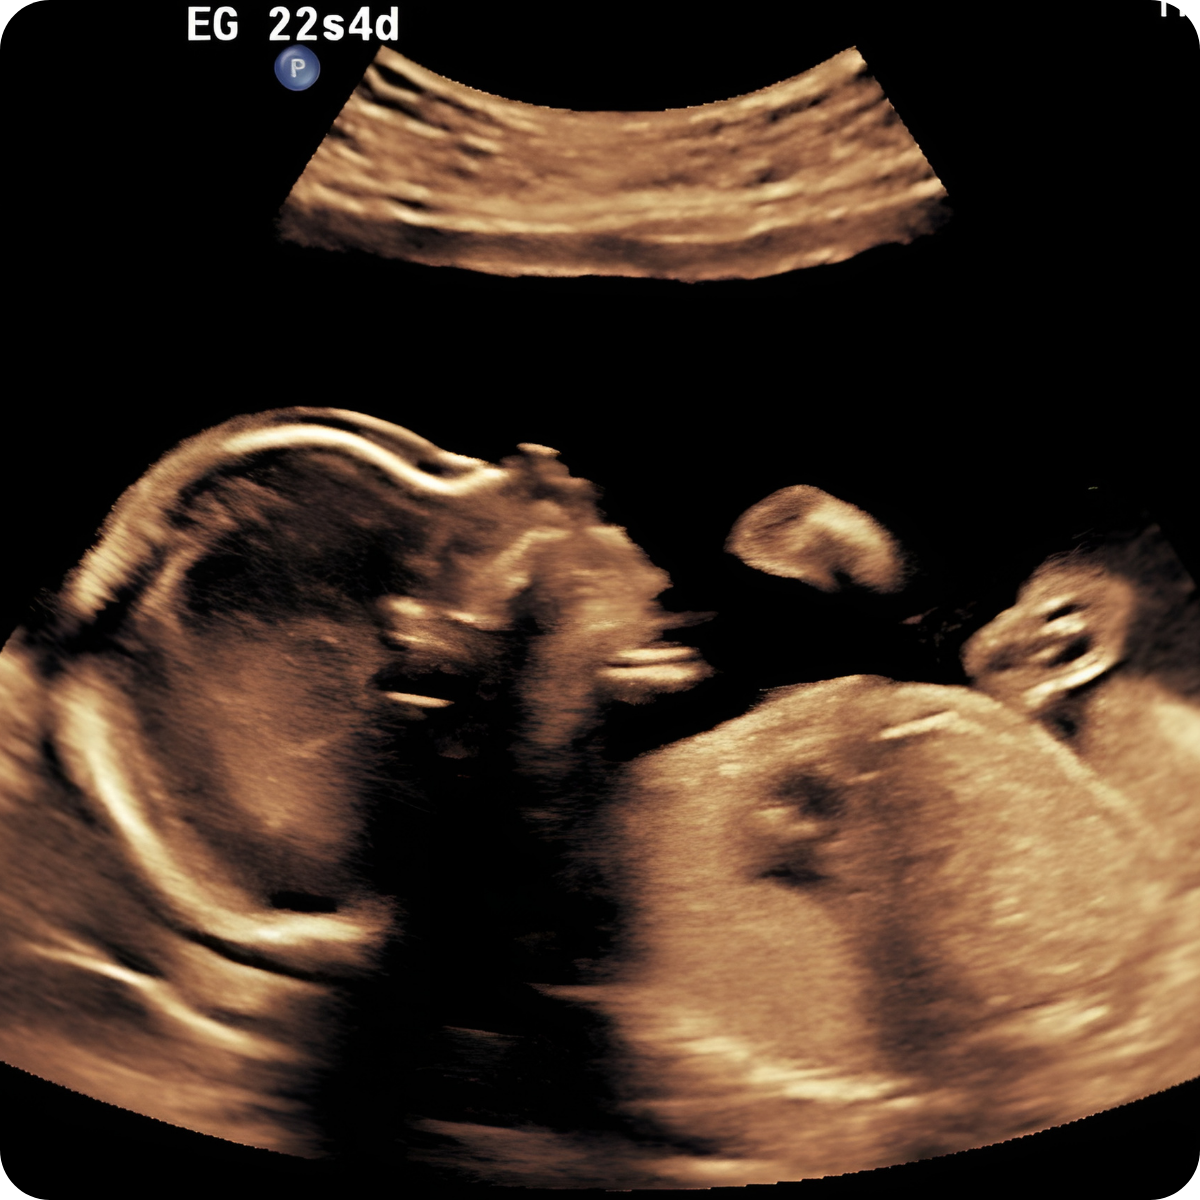

Realizarlo ideal entre las 20 a 24 semanas.

Una de las ecografías más importantes del embarazo. Este es el momento para descartar anomalías fetales de órganos, sistemas y evaluar la circulación placentaria.